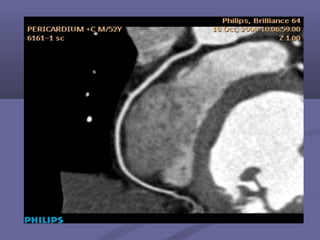

Other Indications:Other Indications:

 TumorsTumors

Other Indications:Other Indications: Post-bypassPost-bypass  Post-stentPost-stent  TumorsTumors